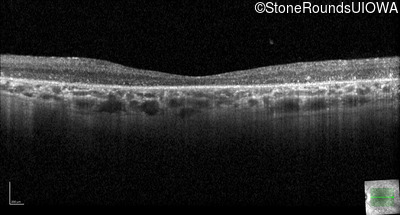

Optical Coherence Tomography - Right - 20/400 sc

Exemplar / OCT Stack

OCT Stack